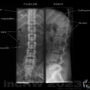

Vad kan man se på en slätröntgen av ländryggen?

All skelett och i viss mån mjukdelar som kommer med på den röntgenbilden. Vid röntgen av ryggraden bländar (zoomar in) man in till en avlång bild så att man inte breddar ut röntgenbilden så att hela buken bestrålas i onödan.

Röntgenstrålen är optimerad för att avbilda skelettet bäst med hög kontrast (obs. ej kontrastmedel!) i denna bild. Om röntgenundersökningen istället gällde en konventionell buköversikt så är röntgenstrålen optimerad för mjuk vävnad med mindre kontrast i bilden.

Det är således inte mycket av bukorganen som kommer med på dessa inbländade bilder av ryggen (se bild). Röntgenbilden anpassas efter vad som ska undersökas.

Om det finns avvikande anatomiska eller patologiska fynd i buken som ligger framför/bakom ryggen i de olika bilderna man tar så kan man eventuellt se detta. Det kan röra sig om stor cysta, uppsvällda tarmslyngor, främmande föremål i tarmen, konkrement” i någondera njure (på sidobilden), mm.